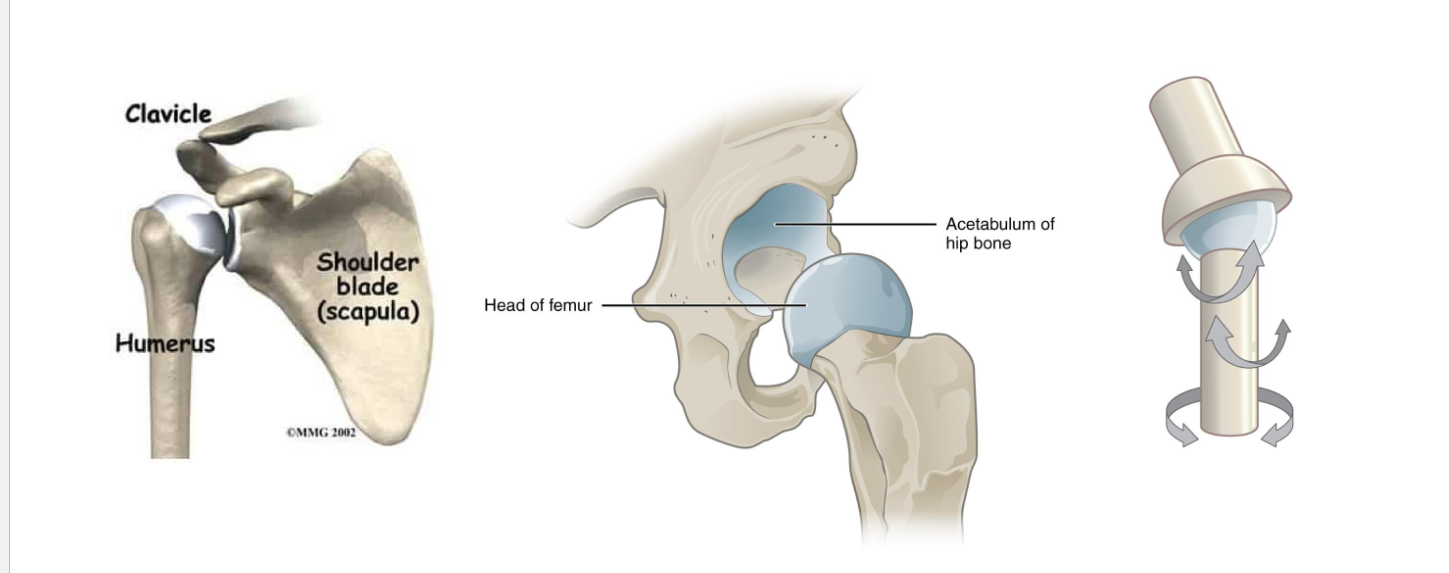

Ball-and-Socket Joints

<p>Ball-and-Socket: shoulder, hip-widest range of motion</p>